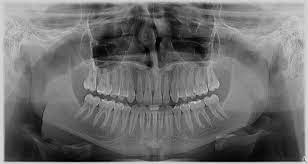

Radiografia Digitală Retroalveolară Denta Film

vizitati articolul complet aici : http://dentafilm.ro/radiografia-digitala-retroalveolara/

Radiografie Dentara Pret Radiografie Panoramica Full Ct

vizitati articolul complet aici : https://www.dentalpremier.ro/radiografie-dentara-pret/

Radiografia Dentară La Copii Cat De Sigură Este Dr Leahu Dental Clinics

vizitati articolul complet aici : https://cliniciledrleahu.ro/radiografia-dentara-la-copii-cat-de-sigura-este/

Fonctionnement, différents types de radios… la radiographie interproximale : La panoramique dentaire est un examen radiologique de première intention dans le diagnostic des pathologies dentaires et buccales. Pour que la radio soit réussie il.